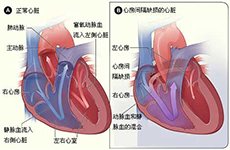

心脏瓣膜病及其他疾病

疾病介绍:心脏瓣膜病及其他疾病心脏瓣膜病就是指二尖瓣、三尖瓣、主动脉瓣和肺动脉瓣的瓣膜因风湿热、黏液变性、退行性改变、先天性畸形、缺血性坏死、感染或创…【详细】

心脏瓣膜病及其他疾病

疾病介绍:心脏瓣膜病及其他疾病心脏瓣膜病就是指二尖瓣、三尖瓣、主动脉瓣和肺动脉瓣的瓣膜因风湿热、黏液变性、退行性改变、先天性畸形、缺血性坏死、感染或创…【详细】

心脏瓣膜病及其他疾病

疾病介绍:心脏瓣膜病及其他疾病心脏瓣膜病就是指二尖瓣、三尖瓣、主动脉瓣和肺动脉瓣的瓣膜因风湿热、黏液变性、退行性改变、先天性畸形、缺血性坏死、感染或创…【详细】

心脏瓣膜病及其他疾病

疾病介绍:心脏瓣膜病及其他疾病心脏瓣膜病就是指二尖瓣、三尖瓣、主动脉瓣和肺动脉瓣的瓣膜因风湿热、黏液变性、退行性改变、先天性畸形、缺血性坏死、感染或创…【详细】

心脏瓣膜病及其他疾病

疾病介绍:心脏瓣膜病及其他疾病心脏瓣膜病就是指二尖瓣、三尖瓣、主动脉瓣和肺动脉瓣的瓣膜因风湿热、黏液变性、退行性改变、先天性畸形、缺血性坏死、感染或创…【详细】

心脏瓣膜病及其他疾病

疾病介绍:心脏瓣膜病及其他疾病心脏瓣膜病就是指二尖瓣、三尖瓣、主动脉瓣和肺动脉瓣的瓣膜因风湿热、黏液变性、退行性改变、先天性畸形、缺血性坏死、感染或创…【详细】

心脏瓣膜病及其他疾病

疾病介绍:心脏瓣膜病及其他疾病心脏瓣膜病就是指二尖瓣、三尖瓣、主动脉瓣和肺动脉瓣的瓣膜因风湿热、黏液变性、退行性改变、先天性畸形、缺血性坏死、感染或创…【详细】